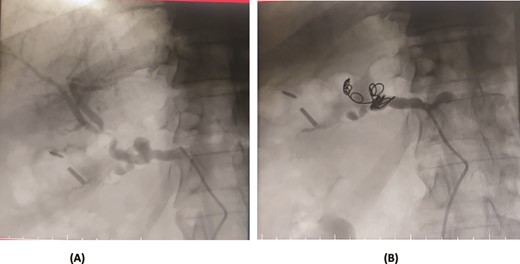

A 66-year-old male underwent an extended cholecystectomy with bile duct excision and Roux-en-Y hepaticojejunostomy for suspected gallbladder carcinoma. However, the histopathological examination revealed xanthogranulomatous cholecystitis. Postoperative patient develops anastomotic site leakage so was discharged with abdominal drain. On the 9th postoperative day, during follow-up for bile leak with an abdominal drain in situ, a contrast-enhanced CT scan of the abdomen identified a pseudoaneurysm at the bifurcation of the gastroduodenal artery and proper hepatic artery. Angioembolization was performed using two coils and 50% glue. The abdominal drain was subsequently removed, and the patient recovered without further complications, doing well at follow-up (Fig. 4).

Case 4. (A) CT scan – pseudoaneurysm at bifurcation of gastroduodenal artery and proper hepatic artery. (B) Embolization of gastroduodenal artery and proper hepatic artery.